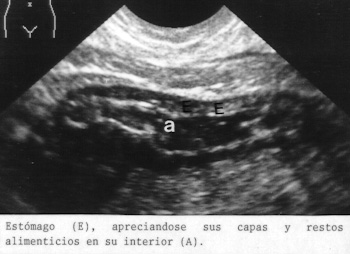

En adultos podemos llenar el estomago con agua ayudados de una aguja y jeringuilla a través del epigastrio. En los niños usamos una sonda nasogastrica y también se suele llenar el intestino. En la Fig 46 el estomago de un niño y el intestino presentan líquido en su interior. En esta imagen son visibles las suprarrenales. En el centro se observa la columna vertebral cortada de través y la médula espinal en el centro.